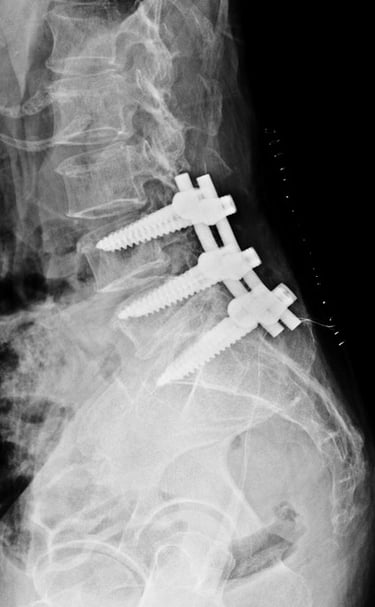

Spine fractures

Expert Surgical/ Non Surgical Care for fractures in the Spine.

Gallery

Explore our advanced spine care visuals.